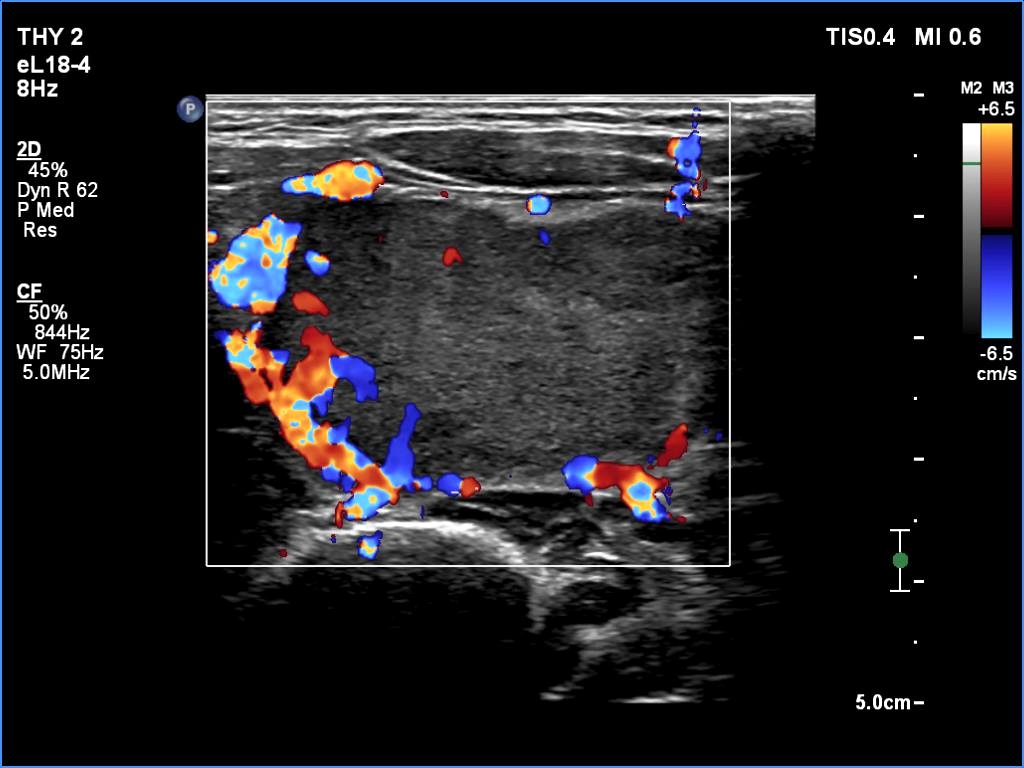

The echogenicity of the nodule - case 365 (ultrasonographic picture 7)

Seven years after the first examination

Left lobe, longitudinal scan, color Doppler mode. Perinodular blood flow prevails over intranodular vascularity.